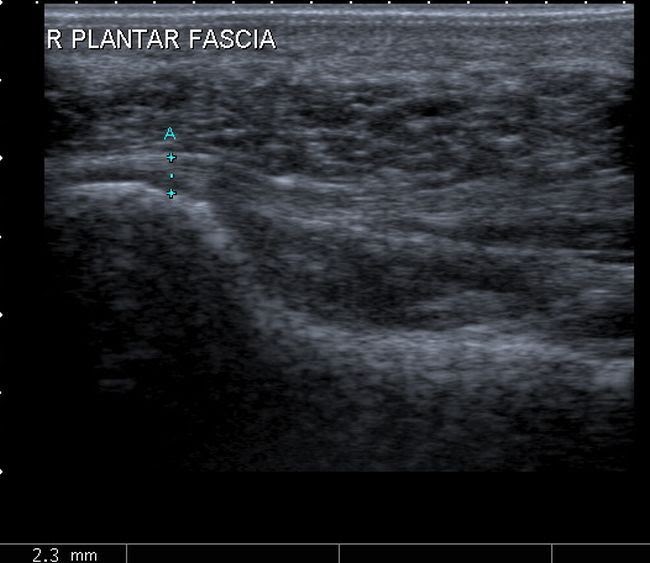

Plantar Fasciitis Ultrasound. Diagnosis is made easier with sonographic machines as they enable marking and measuring of the fascia. Generally, ultrasound examination of plantar fasciitis is performed with the patient in a prone position. 21) and 33 control subjects. Therapeutic ultrasound is one of the most common conservative treatment modalities used by physical therapists worldwide, despite scarce evidence of its efficacy in treating plantar fasciitis.

Pr thickening (> 5mm), fat pad abnormality (narrowed or absent), fine calcification at calcaneal insertion, plantar calcaneal spur at origin. Plantar fasciitis ultrasound observations show the thickening of the fascia over 4mm and a hypoechoic fascia. Musculoskeletal, bone, muscle, nerves and other soft tissues. Diagnosis is made easier with sonographic machines as they enable marking and measuring of the fascia. The purpose of this study is to examine the effectiveness of ultrasound treatment in addition to a program consisting of manual therapy and exercise (stretching and strengthening exercises) to improve pain and function in individuals with plantar fasciitis.

Our primary hypothesis is individuals with plantar fasciitis will show a greater improvement. Heel pain was unilateral in 11 patients and bilateral in four. Thickness decreases on ultrasound with successful treatment. On ultrasound, plantar fasciitis presents with pf thickening (dashed line, 6.5 mm), a hypoechoic appearance and loss of fibrillar pattern (b). It can usually be confirmed by your doctor or physiotherapist using your medical history and examination.

Plantar fasciitis (pf) is a common cause of foot pain, affecting an estimated 2 million people per year.1 although there are large numbers of people seeking medical attention for this condition, there remains some confusion among health care providers as to the most efficacious treatment and some authors conclude that no data solidly supports effectiveness. On ultrasound, plantar fasciitis presents with pf thickening (dashed line, 6.5 mm), a hypoechoic appearance and loss of fibrillar pattern (b). This disorder is related to overuse trauma that leads to microtears. The purpose of this study is to examine the effectiveness of ultrasound treatment in addition to a program consisting of manual therapy and exercise (stretching and strengthening exercises) to improve pain and function in individuals with plantar fasciitis. To investigate the sonographic features of plantar fasciitis (pf).

On ultrasound, plantar fasciitis presents with pf thickening (dashed line, 6.5 mm), a hypoechoic appearance and loss of fibrillar pattern (b). Ultrasound therapy is a relatively new treatment that has gained a great deal of popularity for its low cost, promising results, and minimal downtime. At times, ultrasound has also helped me rule out these most common findings. Ultrasound has afforded me the ability to diagnose fasciitis, fasciosis, plantar fascial tears, inferior calcaneal bursitis, cortical stress fractures and abscesses (with a vertical toothpick embedded in the calcaneus). It can usually be confirmed by your doctor or physiotherapist using your medical history and examination.